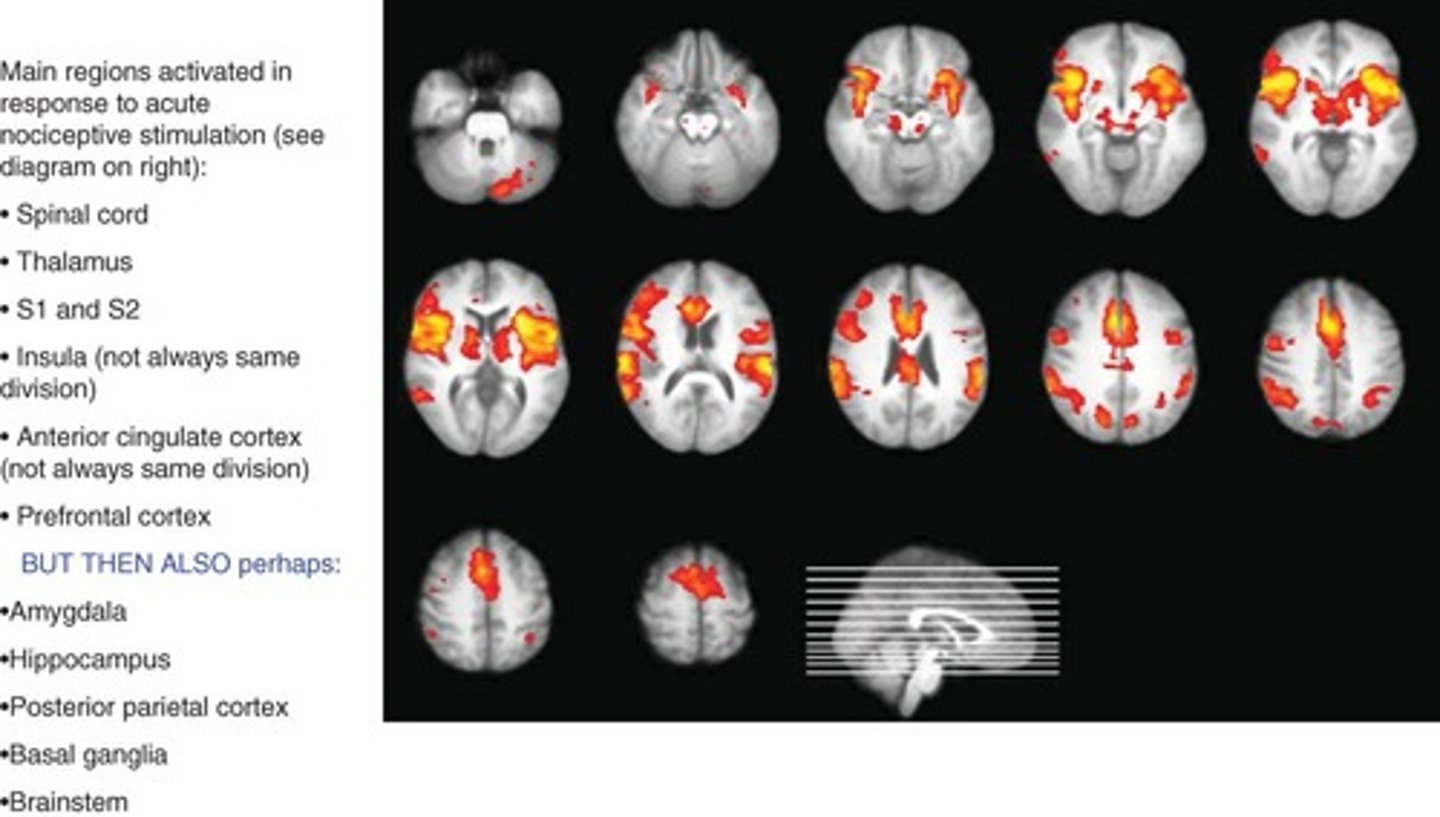

What areas of the brain are involved in nociceptive processing?

Brainstem, thalamus, limbic system, and somatosensory cortex.

What is the Pain Matrix?

It refers to the network of brain regions activated during a painful experience.

What brain regions are activated by painful stimuli?

Primary somatosensory cortex and anterior cingulate cortex.